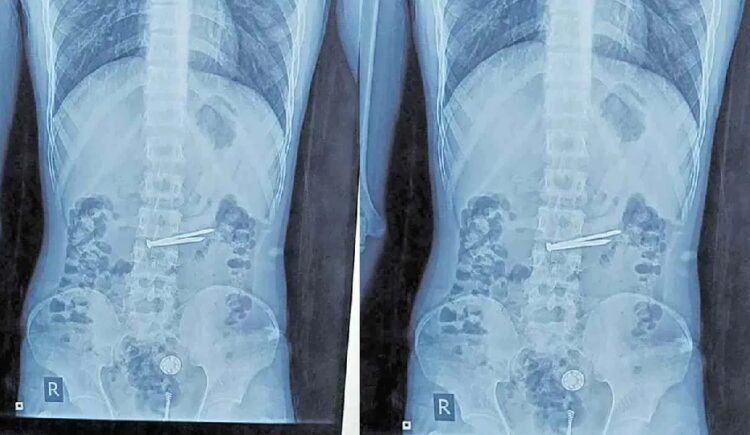

ഹൈദരാബാദ് : വയറുവേദനയുമായെത്തിയ തടവുകാരന്റെ വയറ്റിനുള്ളിൽ നിന്ന് ഡോക്ടർമാർ കണ്ടെത്തിയത് കഞ്ചാവ് പായ്ക്കറ്റുകളും , ഷേവിംഗ് ബ്ലേഡും , ആണിയും . ഹൈദരാബാദ് ചഞ്ചൽഗുഡ ജയിലിലെ 21 വയസ്സുള്ള മുഹമ്മദ് സുഹൈൽ എന്ന തടവുകാരന്റെ വയറ്റിനുള്ളിൽ നിന്നാണ് ഇത്രയേറെ സാധനങ്ങൾ കണ്ടെത്തിയത് .

അടുത്തിടെ മുഹമ്മദ് സുഹൈലിന് കടുത്ത വയറുവേദന അനുഭവപ്പെട്ടിരുന്നു. തുടർന്ന് ജയിൽ ഡോക്ടർമാരുടെ അടുത്തേക്ക് പരിശോധനയ്ക്കായെത്തി . ജയിലിലെ ഡോക്ടർമാർ പ്രാഥമിക ചികിത്സ നൽകിയെങ്കിലും പ്രയോജനമുണ്ടായില്ല. വയറുവേദന കൂടിക്കൊണ്ടിരിക്കുകയായിരുന്നു . തുടർന്ന് പോലീസ് സുഹൈലിനെ ഉസ്മാനിയ ആശുപത്രിയിലേക്ക് കൊണ്ടുപോയി. വിശദ പരിശോധനയും , സ്കാനിംഗും നടത്തിയ ഡോക്ടർമാർ സുഹൈലിന്റെ വയറിനുള്ളിലെ സാധനങ്ങൾ കണ്ട് അമ്പരന്നു.

ഷേവിംഗ് ബ്ലേഡും ആണികളും,രണ്ട് ചെറിയ റബ്ബർ ബോളുകളും പ്ലാസ്റ്റിക് പാക്കറ്റുകളും മറ്റ് ചെറിയ വസ്തുക്കളും പരിശോധനയിൽ കണ്ടെത്തി. വയറ്റിൽ നിന്ന് ഡോക്ടർമാരുടെ സംഘം എൻഡോസ്കോപ്പിയിലൂടെ ഇതെല്ലാം പുറത്തെടുത്തു. വയറ്റിൽ കണ്ടെത്തിയ പ്ലാസ്റ്റിക് പാക്കറ്റുകൾ കഞ്ചാവ് ഉണ്ടെന്ന സംശയത്തെ തുടർന്ന് ലാബിലേക്ക് അയച്ചു.തടവുകാരന്റെ ആരോഗ്യനില ഇപ്പോൾ തൃപ്തികരമാണ്